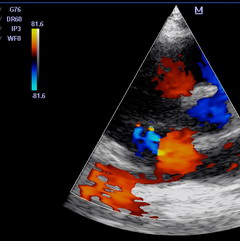

Поставить правильный диагноз при трикуспидальной регургитации, а также определить степень заболевания, можно на основании данных доплеровской эхокардиографии. При трикуспидальной регургитации 1 степени обратный ток крови из правого желудочка обратно в правое предсердие едва заметен. Трикуспидальная регургитация 2 степени характеризуется обратным током крови не более чем на 2,0 см от трехстворчатого клапана. При третьей степени недостаточности регургитация превышает 2,0 см, а при четвертой – распространяется по всему объему правого предсердия.